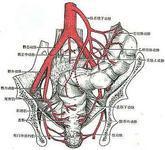

腹部大血管损伤

628健康网为您分享有关腹部大血管损伤的症状,腹部大血管损伤的治疗方法,腹部大血管损伤的预防知识,腹部大血管损伤的症状...

腹主动脉瘤

628健康网为您分享有关腹主动脉瘤的症状,腹主动脉瘤的治疗方法,腹主动脉瘤的预防知识,腹主动脉瘤的症状图片,腹主动脉瘤...

感染性腹主动脉瘤

628健康网为您分享有关感染性腹主动脉瘤的症状,感染性腹主动脉瘤的治疗方法,感染性腹主动脉瘤的预防知识,感染性腹主动脉...